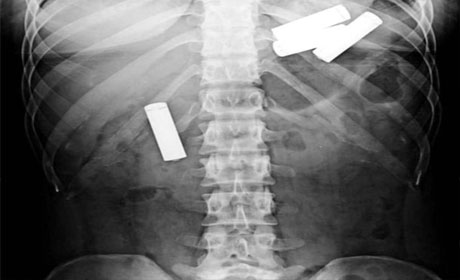

İnsan nələri udmağa qadir deyil? Yaxud mədədən nələr gəlib-keçmir? ANN.Az-in oxuculara təqdim etdiyi fotolar bir daha insanın nələrə qadir olduğunu göstərir. 1. İlan balığı2. Qaşıq3. Batareyalar4. Canlı qurbağa5. Mismar6. Dərmanlar 7. Nişan üzüyü8. Qayçı9. Tük yumağı10. Mobil telefom11. Qələm12. Yay13. Əl bombası14. Açar15. Lampa